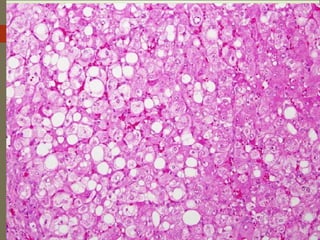

3. Steatosis

Extensive fat infiltration into muscle fibers.

 Fat replaces the content of muscle fibers and the gross muscle

appears to almost completely compose of fat.

The condition may be occur in beef, lamb, pork, etc..